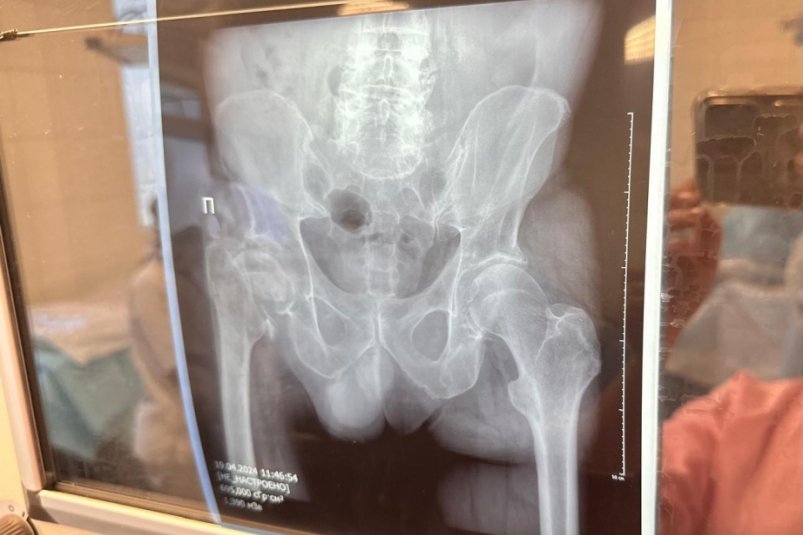

Краевая клиническая больница имени профессора Владимирцева увеличивает количество операций по эндопротезированию тазобедренных и коленных суставов, сообщает ИА AmurMedia со ссылкой на информацию пресс-службы правительства Хабаровского края. Высокотехнологичную помощь при наличии показаний пациенты получают бесплатно по полису ОМС.

Для сравнения — количество операций по эндопротезированию тазобедренных суставов в больнице: в 2019 году — 250, в 2023 году — 675. В первом квартале 2024 года помощь оказали уже 166 пациентам, а план на год — свыше 1000 операций по эндопротезированию.

На этот год всего в больнице запланировано провести свыше 1000 операций по эндопротезированию, больше половины связаны с заменой тазобедренных суставов.

Операция длится около полутора часов, послеоперационный период в стационаре составляет 3-5 дней, затем восстановительная терапия в амбулаторных условиях, около полутора месяцев.